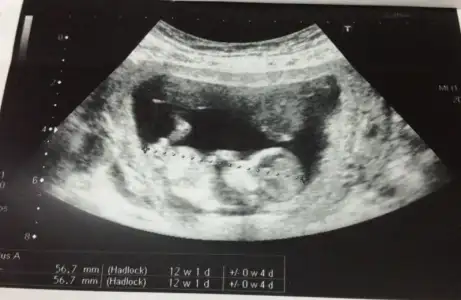

herkese merhaba, bebeğim burada tam 12 haftalık. ikili test için gittiğimde alındı bu görüntü. doktor %50 kız %50 erkek dedi sağolsun. buradan okuduklarım kadarıylada nub göremedim sanki bacak arasında kalmış gibi geldi. çok da merak eiyorum. yorumlarınızı bekliyorum. Eki Görüntüle 976147